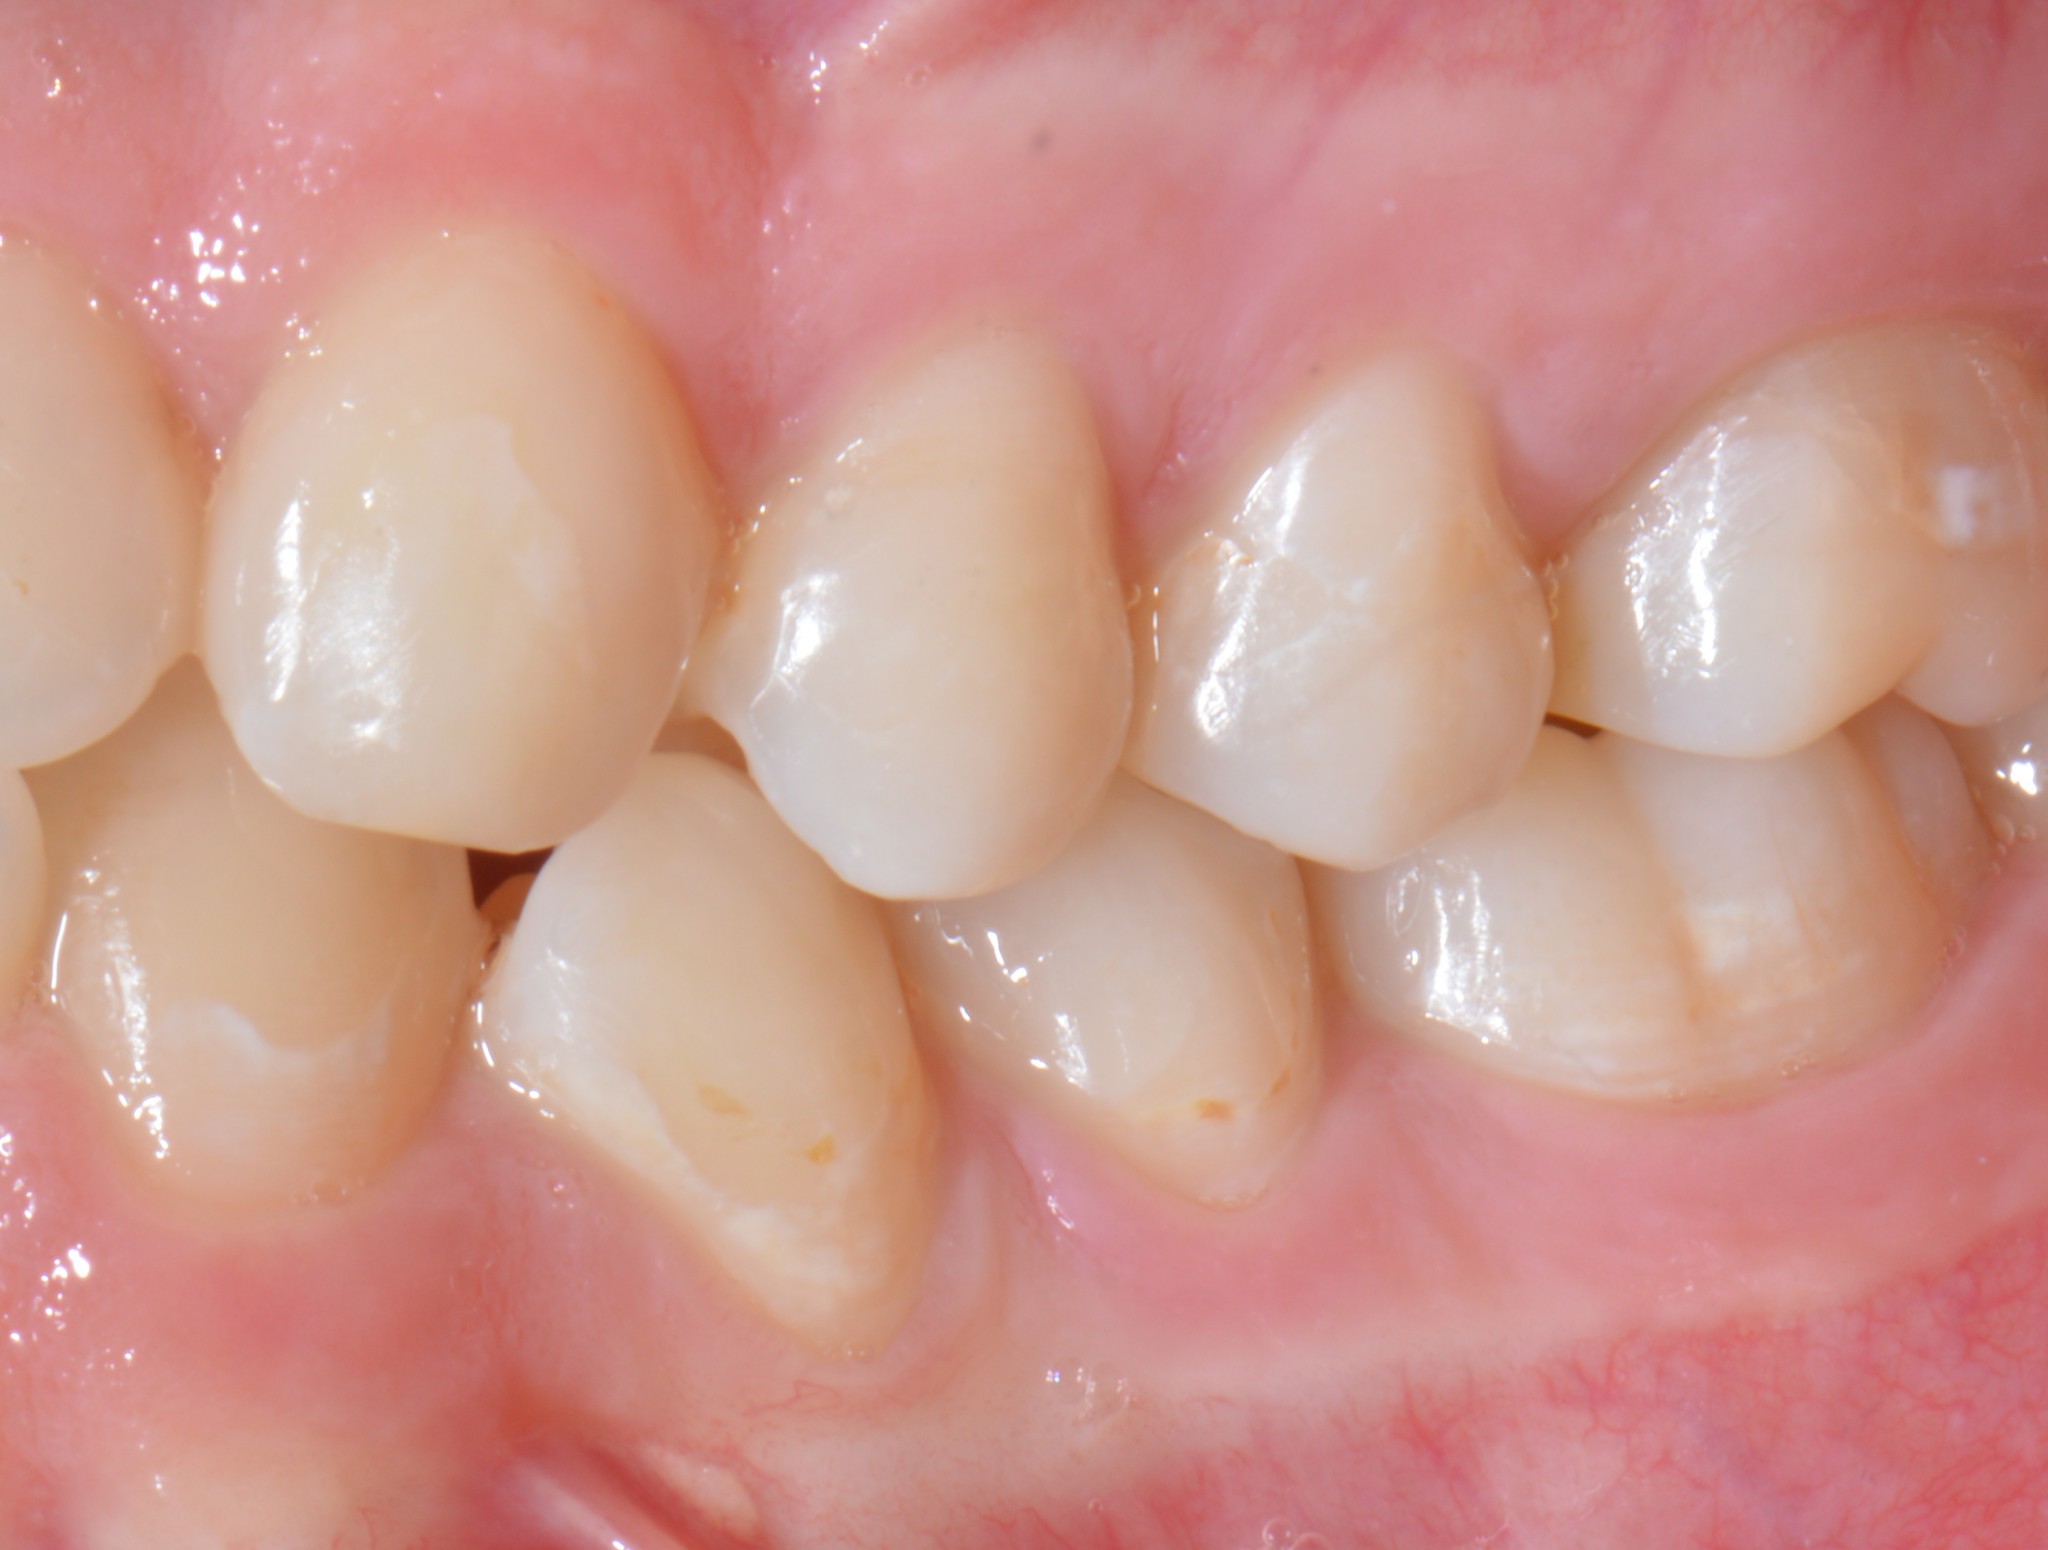

Quando diventi pratico di questa tecnica impari a gestirla in maniera artistica, ottenendo anche degli ottimi risultati in termini di anatomia.

Si può per esempio ricostruire solo il gradino cervicale per un paio di millimetri e poi smontare le matrici e passare all’utilizzo di una normale matrice sezionale.

In certi casi puoi ricostruirti prima e pareti approssimali verticali, per permettere di appoggiare poi un anello siliconico con una normale matrice sezionale che guidi la formazione di un bel punto di contatto.

In altri casi puoi realizzare un build-up completo, poi smontare le matrici ripreparare un box interprossimale e rifare quella porzione con una matrice sezionale utilizzata in maniera tradizionale per dare un corretto punto di contatto.

Come puoi vedere dalle immagini qui sotto, il caso che ho mostrato nella rx precedente a 4 anni di distanza mostra che nè l’osso nè la papilla risentono di questo terribile insulto…